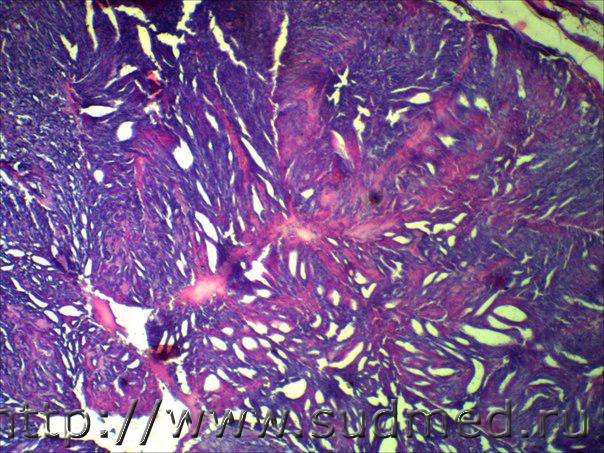

внутрипротоковый рак молочной железы?, опухоль у кошки в области молочной железы

консультация по опухолям М/Ж

Инвазивный протоковый рак. Наверно так.